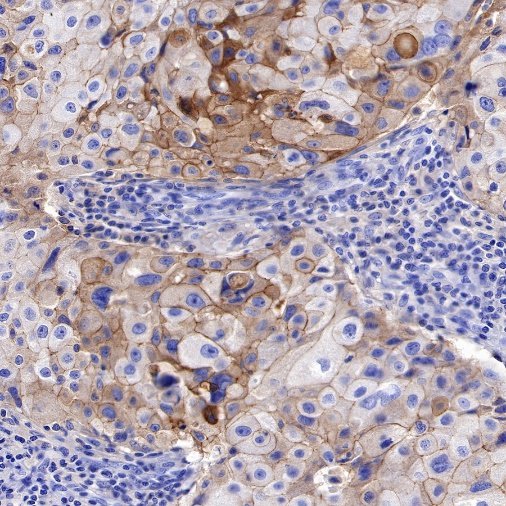

| IHC-P |

1:500 |

Nectin-4 (Nectin cell adhesion molecule 4) is a type I transmembrane cell adhesion molecule belonging to the Nectin family. A homolog formerly known as the poliovirus receptor (PVR/CD155) is also known as the poliovirus receptor associated (PRR) protein. During physiological development, Nectin-4 is specifically expressed during embryonic and fetal development and is very low expressed in adult tissues. It forms physical connections between neighboring cells and is essential for enabling intercellular communication, migration, and other important cellular processes.

Nectin-4 is overexpressed in a variety of tumor cells, and Nectin-4 is used as a marker for cancer recurrence and metastasis, which is associated with poor prognosis of a variety of cancers, including uroepithelial carcinoma, breast cancer, ovarian cancer, pancreatic cancer, non-small cell lung cancer, gastric cancer, hepatocellular carcinoma and bladder cancer. Nectin-4 can promote tumor cell proliferation and differentiation, angiogenesis, lymphangiogenesis and lymphatic metastasis through activation of PI3K/AKT pathway, playing an important role in the occurrence and metastasis of cancer. Nectin-4 is also an independent biomarker associated with poor overall survival in some cancer types. Due to its high specific expression in tumors, drug studies targeting this target have emerged.